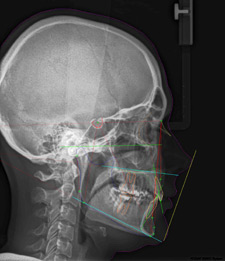

Cephalometric radiograph – an image used to gauge the cranial and facial bones. It allows to detect injuries or damages, diseases and dysmorphism within the area covered by the image. It shows soft tissues of the face, paranasal sinuses and hard palate. In orthodontic treatment it is used to assess the growth of the facial skeleton. What is more, a detailed analysis of these images helps to gauge the spatial relationships of the teeth, jaws and cranium. It is also indispensable to properly diagnose occlusal abnormalities and to plan proper treatment for individual patients. Comparing the image before and after the treatment allows to assess the treatment effectiveness. The image is indispensable to assess the progress in treatment of temporomandibular joints and relaxation of masseter muscles.

Example of cephalometric analysis: